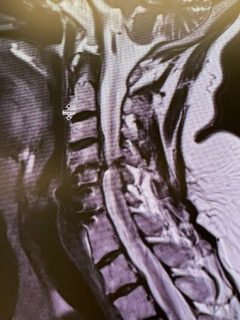

Spine:

Central Cord Syndrome

Author: Yusef Imani M.D., F.A.A.N.S., Read More!